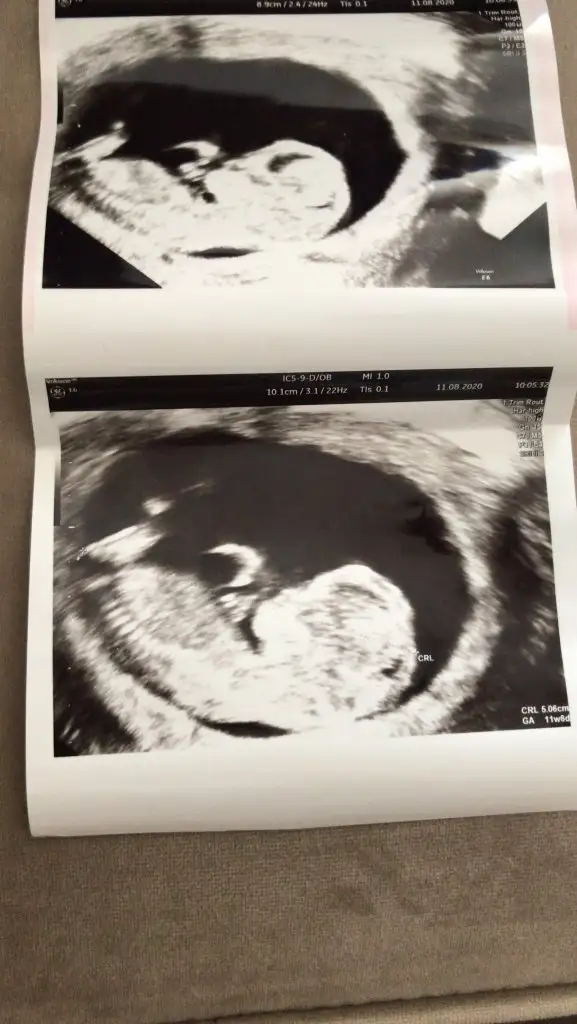

İlk fotoğraf 12+0

İkinci fotoğraf 12+3 (doktor çıkıntı gördüm sanki ama kesin değil dedi)